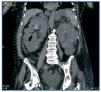

Figura 1. TAC abdominal: corte coronal con quiste complicado en tercio superior de riñón derecho y aire en vía urinaria

Presentamos el caso de una mujer de 76 años, hipertensa, diabética, con insuficiencia renal crónica secundaria a poliquistosis hepatorrenal en programa de diálisis peritoneal desde marzo del 2008 que ingresó por fiebre, disuria y hematuria. Analíticamente presentaba elevación de los parámetros inflamatorios con hemocultivo y urocultivo positivos para E. coli. En una TAC abdominal se observó un quiste en el tercio superior de riñón derecho complicado, con aire en cálices y vejiga sin previa manipulación de vía urinaria (figura 1). Se inició antibioticoterapia de amplio espectro con meropenem y gentamicina, según sensibilidad del antibiograma, y fue transferida temporalmente a hemodiálisis para tratar mejor el cuadro séptico intercurrente. A pesar del tratamiento instaurado, la paciente continuaba estando febril y con deterioro del estado general, por lo que se realizó un nuevo control tomográfico en el que se observó un empeoramiento del quiste de riñón derecho. Dada la mala evolución clínica del cuadro séptico con ausencia de respuesta al tratamiento, se realizó una nefrectomía radical derecha, donde se apreció riñón con múltiples quistes llenos de material purulento (figura 2). La evolución posterior fue lenta hacia la mejoría del estado general, con práctica resolución de la fiebre y progresiva normalización de los parámetros inflamatorios. Finalmente, la paciente pudo ser dada de alta tras un largo período de convalecencia, en situación de estabilidad clínica y hemodinámica, continuando su terapia sustitutiva renal mediante hemodiálisis periódica.